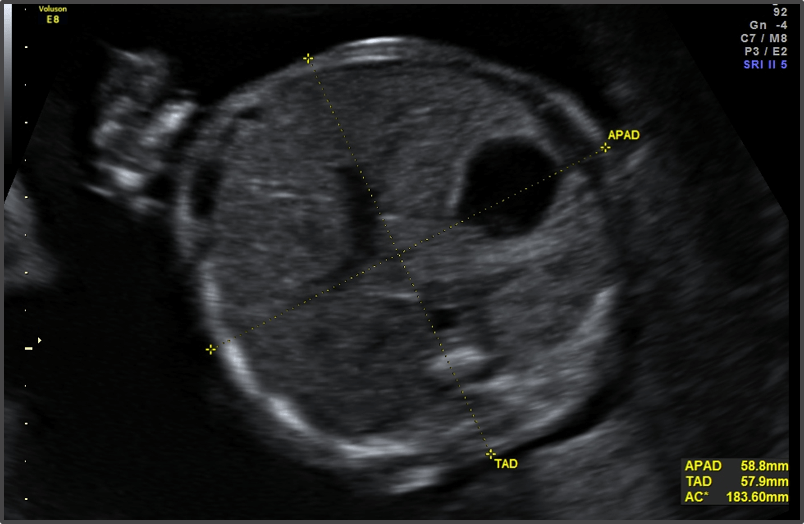

The baby’s skin is becoming more opaque.

Approx Baby Weight: 430g

Approx Baby Size: 27.8 cm